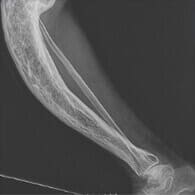

Consecințele și riscurile bolilor articulare

care apar dacă nu tratați bolile, ci simptomele

Deformarea oaselor

Durere insuportabilă

Paralizie

Pierderea completă a capacității de a se mișca

Artrită și artroză Durere la mișcare și în repaus. Mișcare cu dificultăți. Uneori - roșeața pielii, creșterea temperaturii. Deformarea articulației. Distrugerea țesutului osos. Imobilitate completă.

Osteocondroză și osteoporoză Amorțeală periodică a membrelor. Dureri de spate și coloanei vertebrale. Durere în inimă și coaste. Deteriorarea fixării vertebrelor. Hernii. Tulburări vasculare. Invaliditate.

Bursită Umflare severă în zona articulației deteriorate. Mobilitatea afectată a articulației sau imobilitatea completă a membrelor. Senzații dureroase la apăsare. Roșeața pielii cu margini indistincte în zona tumorii. Inflamația țesutului osos. Formațiuni purulente. Otrăvirea sângelui. Imobilizarea completă a articulației.

Sinovită Rigiditatea mișcărilor. Senzații neplăcute, umflături în zona afectată. Extinderea și deformarea articulației afectate. Creșterea temperaturii locale și generale a corpului. Distrugerea articulației. Paralizie. Otrăvirea sângelui. Se întâmplă decese.